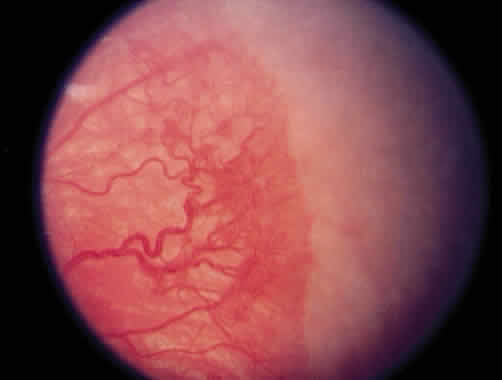

Progressive vascular incompetence, occurring with the changes at the edge of the abnormally developing retinal vasculature, is noted by increasing dilation and tortuosity of the peripheral retinal vessels, iris vascular engorgement, pupillary rigidity, and vitreous haze. When the vascular changes are so marked that the posterior veins are enlarged and the arterioles are tortuous, a plus sign is added to the ROP stage number (Fig. 4). Subsequent to the initial ICROP report, completion of the classification of ROP led to the publication of the classification of retinal detachment.41 Stage 4 was expanded to stage 4A and 4B. Stage 4A (Fig. 5) represents extrafoveal retinal detachment, which is a concave traction type of retinal detachment in the periphery without involvement of the macula. These detachments generally are located in anterior zone II or III. Stage 4B (Fig. 6) is a partial retinal detachment including the fovea, which usually extends in the form of a fold from the disc through zone I to involve zones II and III. Stage 5 retinal detachments are total and always funnel shaped. Stage 5 is subdivided based on the shape of the funnel. The funnel is divided into anterior and posterior parts, allowing for four subdivisions, depending on whether the funnel is open or narrow in both parts of the funnel.

Fig. 5. Stage 4A retinopathy of prematurity.